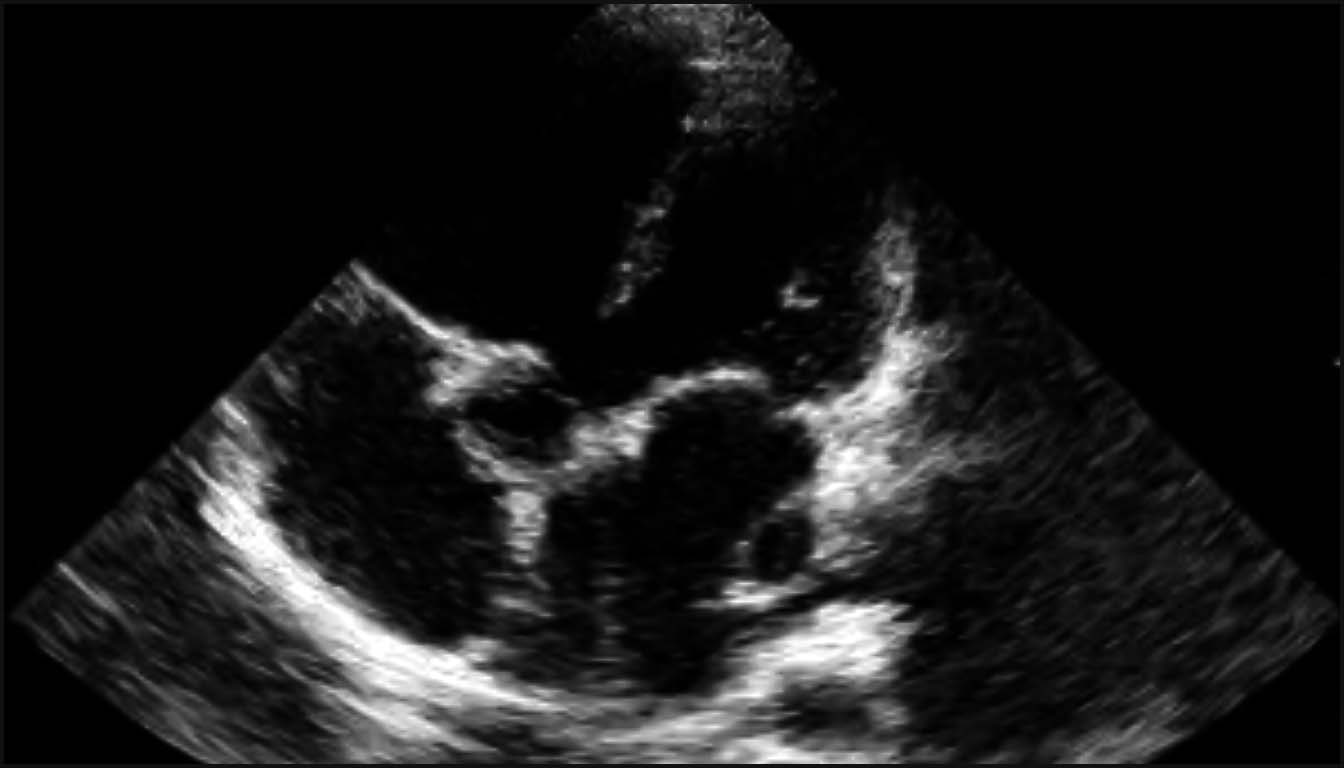

1. La Coupe des Quatre Cavités (4C) : Fondements de l’Analyse

La coupe 4C est la base de l’examen, permettant de détecter environ 50 % des CC majeures. Un examen normal doit confirmer plusieurs éléments critiques :

• Situs et Position : Le cœur doit être situé majoritairement dans l’hémithorax gauche avec l’apex pointant à gauche selon un axe de 45° ± 20°. Un axe anormal est un signe d’appel fort pour des anomalies des voies d’éjection ou des anomalies chromosomiques.

• Taille Cardiaque : Le cœur doit normalement occuper environ un tiers de la surface thoracique. Un rapport cardiothoracique augmenté (cardiomégalie) est souvent le premier signe d’une insuffisance valvulaire sévère ou d’une dysfonction myocardique.

• Symétrie et Structure : Les deux oreillettes et les deux ventricules doivent être de taille approximativement égale en milieu de gestation. Une disproportion ventriculaire (VD > VG) est un signe suspect pour une coarctation de l’aorte ou un syndrome d’hypoplasie du cœur gauche (SHCG).

• La Croix du Cœur : L’intégrité de la croix du cœur, avec le décalage normal des valves auriculo-ventriculaires (la tricuspide s’insérant plus près de l’apex que la mitrale), doit être visible. L’absence de ce décalage est caractéristique d’un canal atrioventriculaire (CAV).

Le dépistage s’effectue traditionnellement lors de l’échographie morphologique du deuxième trimestre (18-22 semaines). Historiquement, l’examen se limitait à la coupe des quatre cavités (4C), mais celle-ci ne permet de détecter que 26 % à 50 % des malformations cardiaques majeures, manquant notamment les anomalies des gros vaisseaux.

2. La coupe des quatre cavités : évaluation de la taille, de l’axe cardiaque (45° ± 20°) et de la symétrie des ventricules et des oreillettes.

1. Le Situs : On vérifie d’abord que l’estomac et le cœur sont bien situés à gauche. Un axe cardiaque anormal (normal : 45° $\pm$ 20°) est souvent le premier signe d’une cardiopathie complexe.

2. Connections AV : La coupe 4C permet d’évaluer la symétrie des ventricules et l’intégrité de la croix du cœur. Un déséquilibre de taille entre le ventricule gauche (VG) et le ventricule droit (VD) doit faire suspecter un syndrome d’hypoplasie du cœur gauche (HLHS) ou une coarctation de l’aorte.